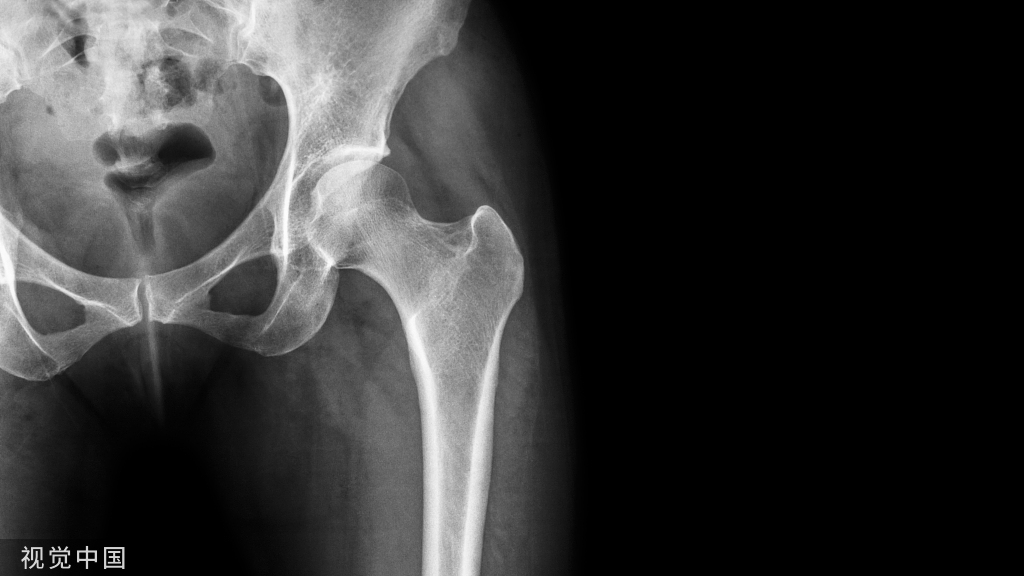

膝关节骨关节炎是人类最常见的骨科疾病之一,根据牛津大学最新的数据统计,在骨科门诊每四个具有严重膝关节疼痛症状的骨关节炎患者当中,只有一个适合于膝关节置换,而另外三个都可以通过保膝的手术来进行治疗。

适合截骨的患者,软骨磨损从0到4级,术后效果都很好,尤其是磨损比较重的3和4级患者,效果更明显。只要适应症符合,截骨患者的术后疼痛缓解和膝关节功能的综合评分表现,优于膝关节置换。

Philipp Lobenhoffer的研究发现KL0-4期症状的患者,术后效果都明显改善,KL3-4期患者效果改善更明显,多中心的研究显示HTO的OKS评分优于膝关节置换。也有很多研究指出,关节炎的轻重与效果无明显差别。

只要适应症合适,内侧骨关节伴有内翻,做完手术都会很有效的。截骨手术用于治疗中重度关节炎是目前截骨技术的重要进展,也是经过大量研究和临床证实确切有效的治疗方法。

目前的截骨技术精确,根据关节炎的轻重可以决定矫正的程度。矫正不足会出现症状缓解时间有限,矫正过度会加重外侧关节炎,远期效果不佳。

因此,矫正手术的精确性保证了中重度关节炎的良好的近期和远期疗效。如前第一点所述,伴有内翻畸形的内侧关节炎,通过矫正手术,内侧减压后症状会明显缓解。对于关节软骨磨损越重的患者,我们矫正的程度越大,内侧应力降的越低,疼痛缓解明显。